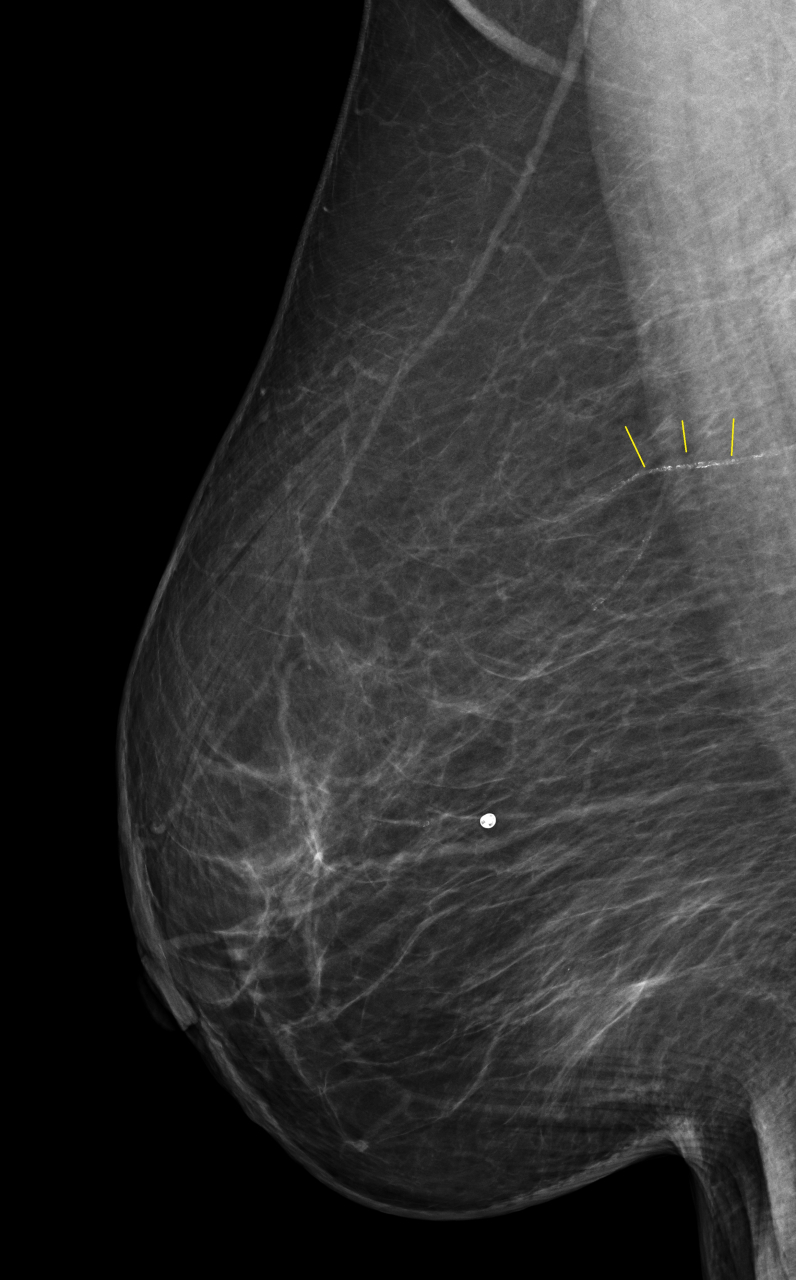

上記のMMGにおいて 黄色い線で示しているところは乳腺の動脈です。そこに沿って白い小さな点がびっしりと認められます。この動脈に”動脈硬化”が発生し、そこに石灰(カルシウム)が沈着することで描出されるようになったものです。